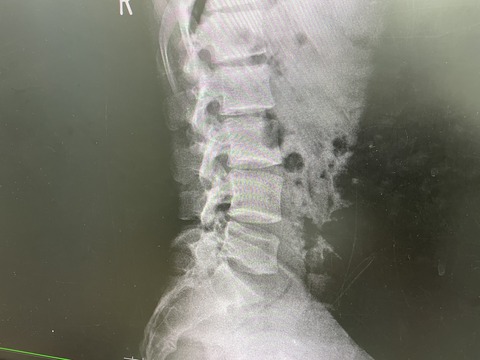

ツアープロゴルファー選手

背部の痛みを取れなくて、来院

肩甲骨周囲筋、上腕三頭筋ををほぐして、

注射で筋肉を和らげての、治療を行い

来週ぐらいから、フルスイングを目指します